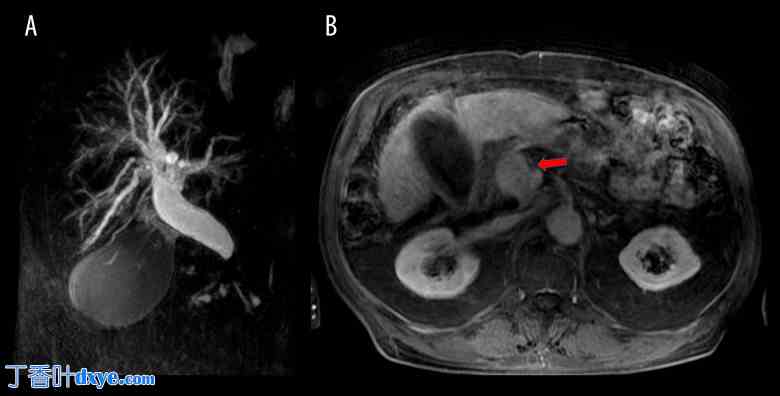

此外,还进行了磁共振胰胆管造影 (MRCP) 检查,证实胰体尾完全缺失。MRCP 报告显示,远端胆总管严重阻塞,原因是胰头肿块不均匀,很可能是肿瘤来源。脾系膜肠静脉汇合处后方发现一个大型淋巴结。未观察到继发性局灶性肝脏病变的证据。胆囊扩张也可见(图 2)。

图 2.

MRCP 显示胰头肿块不均匀导致远端胆总管严重梗阻 (A),导致肝内外胆管明显扩张。胆囊明显扩张,符合胆汁淤积征象。轴向 T2 加权 MRI 扫描 (B) 显示胰体尾严重萎缩,胰腺背部实质缺失,证实了 ADP 的诊断。红色箭头指示胰头内一个巨大且不均匀的肿块,压迫胆总管并导致胆道梗阻。